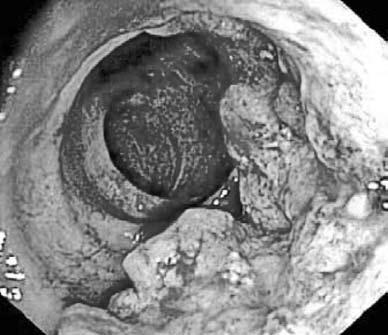

Рис. 183. Рак ободочной кишки.

Эндоскопическая картина 3) неровности контура кишки, атипичного рельефа слизистой, обрыва складок и отсутствие гаустр в области поражения;

Фиброколоноскопия (ФКС) – это метод осмотра слизистой оболочки толстой кишки с помощью специальных гибких эндоскопов с волоконной оптикой (рис. 183). С целью морфологической верификации опухоли во время колоноскопии может быть выполнена прицельная биопсия слизистой оболочки.

Метод фиброколоноскопии достаточно безопасен, хотя его проведение и представляет значительные методические трудности и требует от эндоскописта определенного мастерства. Это объясняется, прежде всего, анатомическими особенностями толстой кишки, которая имеет целый ряд естественных изгибов и физиологических сфинктеров. Перед фиброколоноскопией необходимо произвести ректороманоскопию и пальцевое исследование прямой кишки (подробно методики ректороманоскопии и пальцевого исследования описаны в главе «Заболевания прямой кишки»).

Эндоскопическое исследование с прицельной биопсией при раке толстой кишки позволяет не только существенно повысить процент выявления опухолей этой локализации (на 20–30 % по сравнению с данными ирригоскопии), но и установить гистологическое строение опухоли, что имеет значение для выбора объема оперативного вмешательства, а также определения прогноза заболевания.